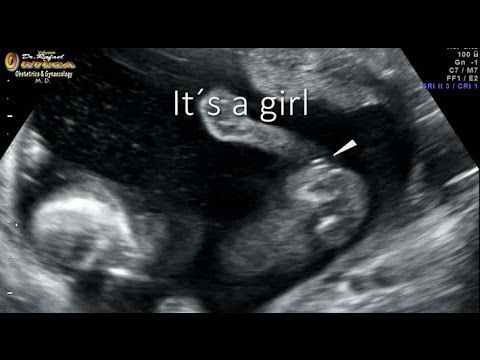

Ультразвуковое исследование (УЗИ) стало неотъемлемой частью наблюдения за беременностью, но даже эта передовая технология не застрахована от ошибок. Особенно интригующим аспектом является определение пола будущего ребенка. Многие будущие родители с нетерпением ждут момента, когда смогут узнать, кто у них родится – мальчик или девочка. Но что делать, если УЗИ говорит одно, а природа преподносит совсем другой сюрприз?

Представьте себе ситуацию: вы уже подготовили розовую комнату, купили кучу платьиц и заказали торт с надписью «Это девочка!» на праздник по случаю определения пола. И вдруг – бац! – а узи сказали девочка а родился мальчик. Как такое возможно? Давайте разберемся в этом удивительном феномене.

Прежде всего, стоит отметить, что УЗИ – это не волшебная палочка, а сложный технический процесс, зависящий от множества факторов. Точность определения пола во многом зависит от срока беременности, опыта врача, качества оборудования и даже от положения плода в момент исследования. Иногда природа словно играет в прятки, скрывая важные детали от любопытных глаз.

Одна из главных причин ошибок – это слишком ранний срок проведения исследования. До 16-й недели беременности половые органы плода еще недостаточно сформированы, чтобы можно было с уверенностью говорить о поле ребенка. В этот период гениталии мальчиков и девочек выглядят практически одинаково, что может привести к неверной интерпретации.

Другой фактор – это положение плода. Иногда малыш может занять такую позу, что его половые органы оказываются скрыты от датчика УЗИ. Представьте, что вы пытаетесь разглядеть что-то через мутное стекло – вот примерно так же врачу приходится «всматриваться» в изображение на экране, пытаясь определить пол будущего ребенка.

Интересно, что статистика ошибок при определении пола не симметрична. Чаще встречаются случаи, когда девочку принимают за мальчика, чем наоборот. Это связано с тем, что пуповина или ножки плода могут быть приняты за мужские гениталии. А вот случаи, когда а узи сказали девочка а родился мальчик, встречаются реже, но все же бывают.